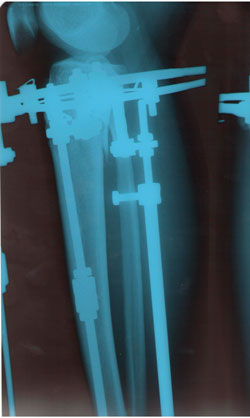

Рентген в 2 месяца.

Сращение отличное, снимать можно в первых числах апреля, но Н.Н. будет отсутствовать с 1 - 14 апреля. По этому, рекомендую приехать на снятие аппаратов 15 апреля (так будет лучше).